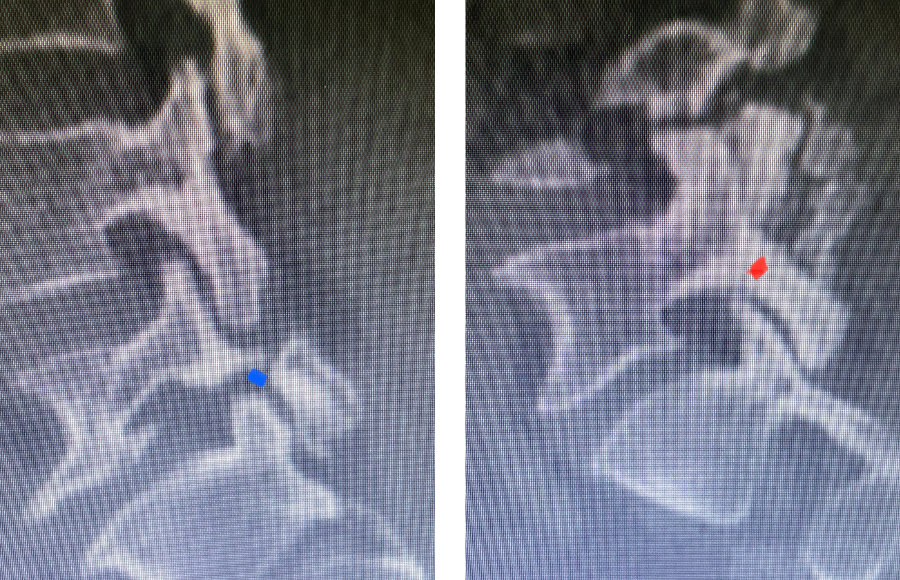

Fig 2: Sagittal T2-weighted MRI of the lumbar spine demonstrating a dysmorphic, trapezoidal-shaped L5 vertebral body (red dot) and a subtle grade 1 spondylolisthesis L5-S1 (blue line).

Fig 3: Sagittal CT scan with bone windows demonstrating an L5 pars defect (blue dot) and abnormal L5-S1 facet complex as well as a normal right pars structure of L5 (red dot).

Another interesting 54-year-old patient presented with low back pain and severe left lower extremity pain over two months. He had a history of falls. The pain in the leg was more bothersome to the patient. The patient had a work-up with an MRI and CT of the lumbar spine. MRI demonstrated a subtle grade 1 spondylolisthesis L5-S1 with a dysmorphic L5 vertebral body (Fig 2). There was a suggestion of a left L5 spondylolysis or defect in the bridge of bone that connects the superior facet process of the segment and the inferior facet process. A CT of the lumbar confirmed this unilateral abnormality which certainly could account for the patient’s left leg pain (Fig 3). This is an unusual finding in that most patients have bilateral pars defects. Patients with L5-S1 often have congenital abnormalities of the lumbosacral junction including weird shaped, elongated or dysplastic facet joints. A subtle L5-S1 spondylolisthesis with an associated smaller and misshapen L5 vertebral body is often associated with L5 spondylolysis. In addition, with a dysmorphic L5 vertebral body, there is secondary disc degeneration at L5-S1 and sometimes at the L4-5 disc with an associated retrolisthesis at L4-5. There is less surface to surface contact of the L4-5 and L5-S1 leading to chronic segmental instability.